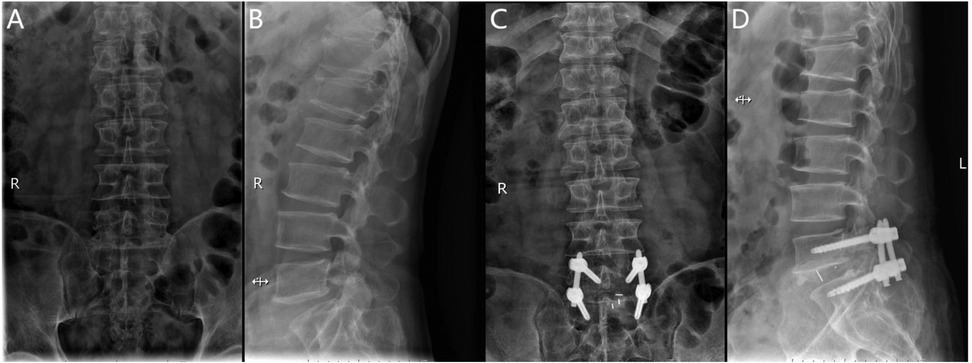

The Endo-PLIF (full-endoscopic posterior lumbar interbody fusion) is a minimally invasive procedure performed under endoscopic guidance. After anesthesia, the patient is positioned prone on a fluoroscopy table. Using a C-arm x-ray machine, the spinous process, bilateral pedicles, and disc levels of the affected segment are identified, and corresponding landmarks are marked on the skin, typically 2–4 cm lateral to the midline. A guidewire for the pedicle screw track is placed under C-arm fluoroscopic guidance and left in place. The positioning needle is inserted through the junction of the articular process and lamina, maintaining parallel alignment with the intervertebral space. Following sequential dilation, the Endo-Surgi Plus endoscope is introduced, and its position is confirmed via C-arm fluoroscopy, with the dilator sheath removed. The soft tissues overlying the lamina and caudal articular process are cleared to expose the transition zone between these structures. Using a bone cutter or rongeur under endoscopic visualization, the lower articular process, inferior lamina, inner margin of the articular process, and the root of the spinous process are resected sequentially, ensuring complete release of the ligamentum flavum bilaterally. If necessary, partial removal of the superior articular process is performed to expose the intervertebral disc, ipsilateral nerve root, and lateral recess. The small joints and the ipsilateral posterior lamina are progressively removed. Autologous bone is prepared for interbody grafting. Under direct visualization, the intervertebral disc tissue is removed using rongeurs and curettes, with the cannula rotated to protect the nerve roots. After disc removal, the endplate is prepared under endoscopic guidance until slight bleeding is observed from the bone surface. A larger cannula is inserted, with the “tongue” rotated inward to protect the dura mater. Autologous and allograft bone are packed into the intervertebral space using a bone graft funnel, and a visual fusion device is inserted, positioned under C-arm fluoroscopic control. Finally, pedicle screws are inserted along the guidewire, with C-arm fluoroscopy confirming correct screw positioning. The bilateral connecting rods are vertically installed and tightened, followed by irrigation of the incision and suturing (Figure 2).

Figure 2. (A) Preoperative anteroposterior radiograph of the lumbar spine; (B) preoperative lateral radiograph of the lumbar spine; (C) postoperative anteroposterior radiograph showing spinal instrumentation; (D) postoperative lateral radiograph showing spinal instrumentation.